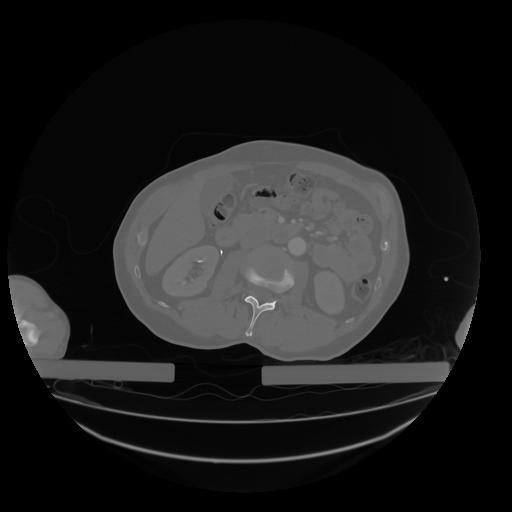

28 CUERPO,CE,Vol,2.0,CUERPO,,